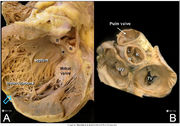

| 10:21, 18 May 2012 | Figure1.jpg (file) |  |

1.06 MB | 1 | |